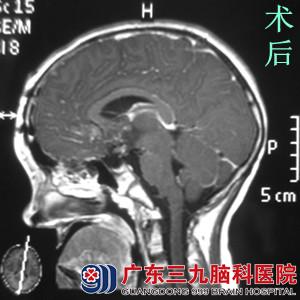

小新近日来广东三九脑科医院 综合神经外科 鲁明主任处就诊。行头颅MR检查提示鞍区占位,考虑颅咽管瘤可能行大。完善相关检查后,由鲁明主任主刀,在全麻下行右额前纵裂入路鞍区颅咽管瘤切除术后,术中显微镜下见黄白色肿瘤组织,予肿瘤全切,手术顺利结束。术后小新经过专科治疗及护理,未出现尿崩、离子紊乱、下丘脑反应等术后并发症,康复出院。术后病理结果:颅咽管瘤。

颅咽管瘤是儿童及青年最常见的先天性良性肿瘤,男女比例约为2:1。临床表现主要为颅内压增高征、双侧视力减退、视野缺损、内分泌功能障碍及下丘脑症状。手术治疗为首选,年龄越小,越易全切,并发症越少,故早诊早治是关键。